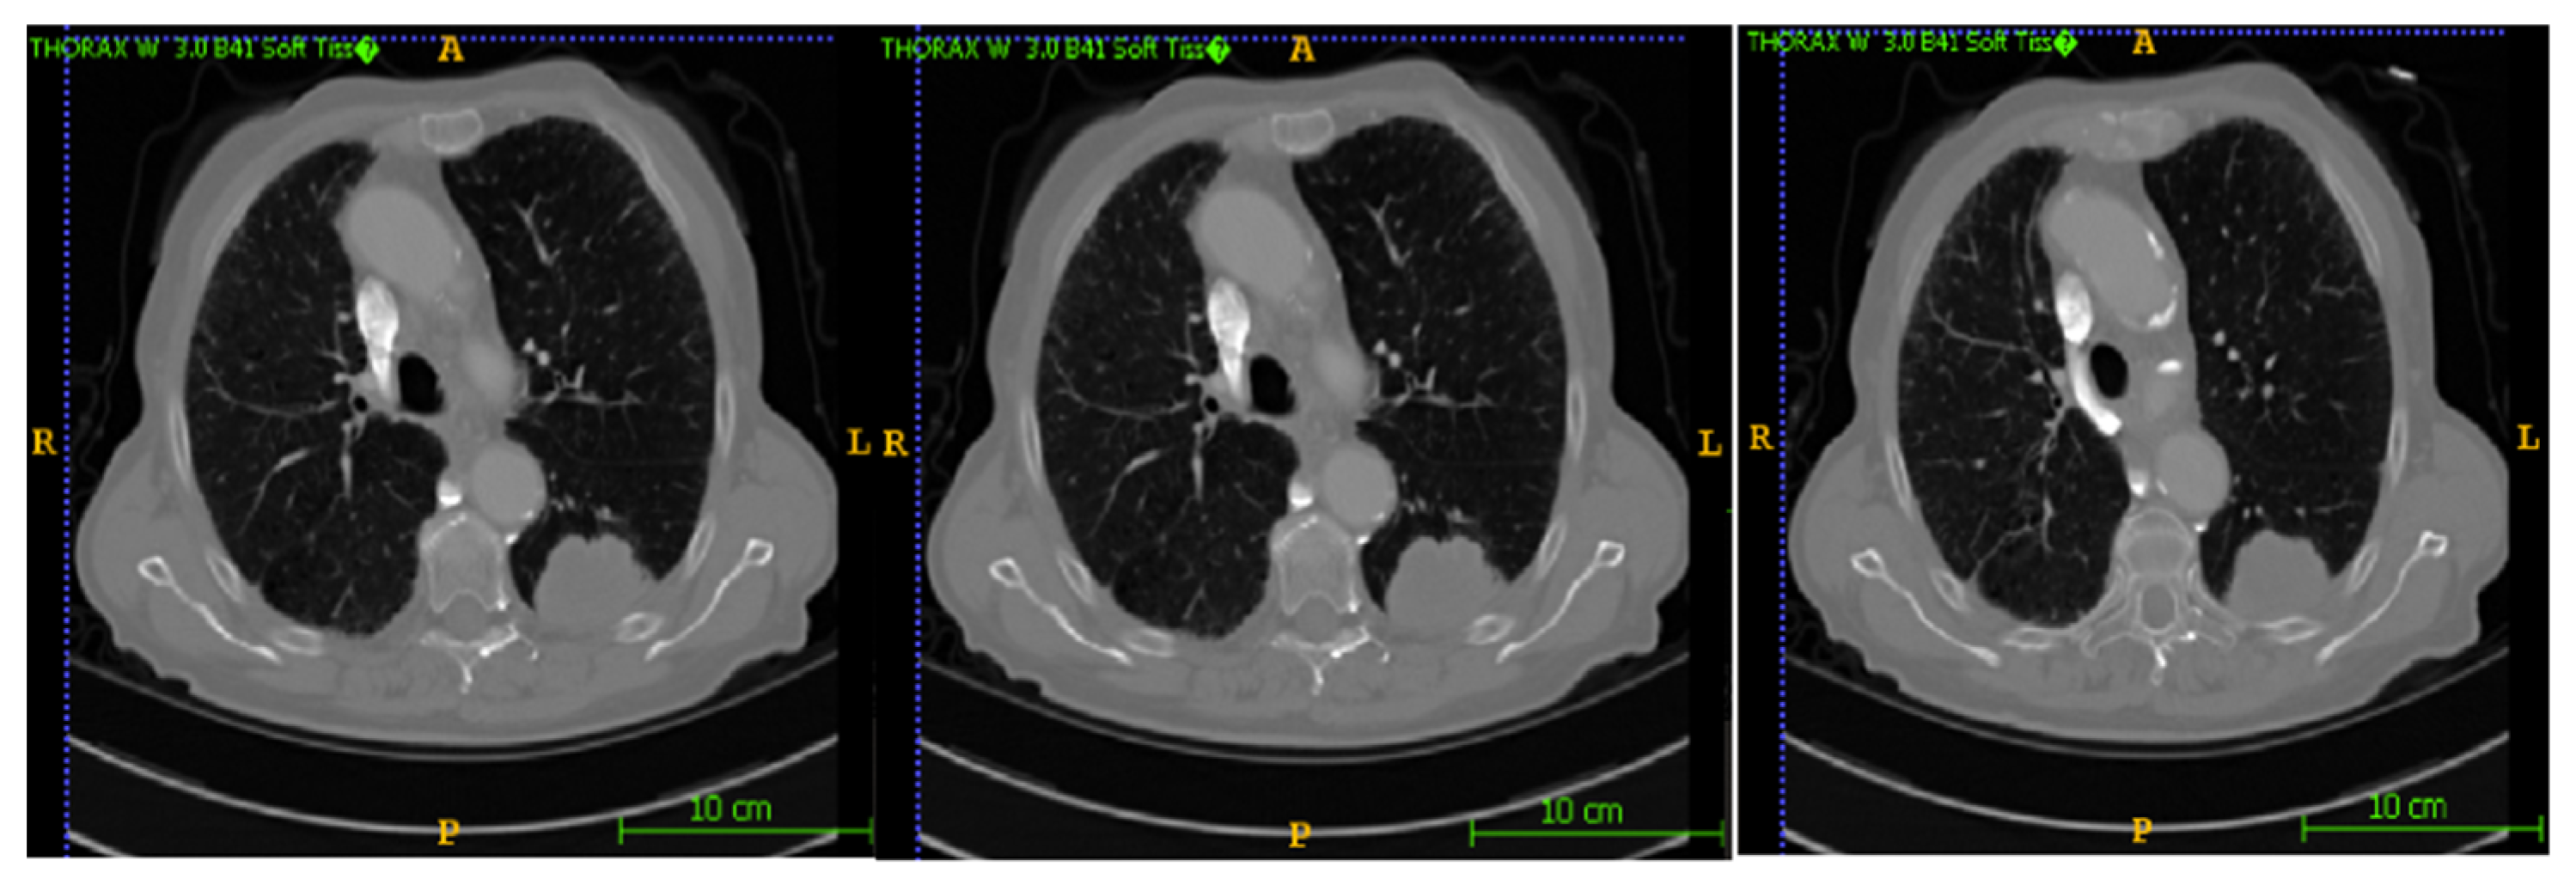

In this section, the segmentation results of the RW-ensemble are visualized for distinct types of nodules. The results for three different types of nodules from the LCT-D dataset are demonstrated: solid nodules, juxta-vascular, and pleural nodules. To improve clarity, each case is visualized through CT slices and the corresponding RW-ensemble segmented outputs, organized by nodule type and patient ID. Figure 6 and Figure 7 represent the solid nodule and its respective RW-E segmented images in grey-scale for patient R_0108. The juxta-vascular nodules of patient R_0052 are shown in Figure 8, and the corresponding RW-E segmented output images are illustrated in Figure 9. Juxta-pleural nodules, which are challenging due to their attachment to the lung wall, are illustrated in Figure 10 and Figure 11 for patient QIN_LSC_0064.

Figure 6. CT slices showing a solid lung nodule (Patient R_0108).

Bioengineering 12 00576 g006

Figure 8. CT slices showing juxta-vascular nodules (Patient R_0052).

Bioengineering 12 00576 g008